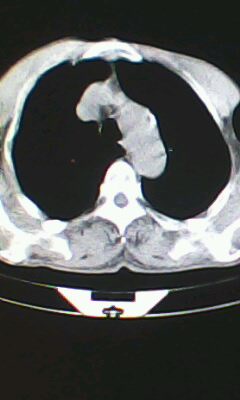

标题: CT26182:男 胸憋 无其它异常症状

胸廓呈桶状,双膈低平,肺实质及纵隔未见明显异常密度灶考虑肺气肿.

肺气肿

以下是引用ctkz987在2010-5-5 21:30:00的发言:[br]胸廓呈桶状,双膈低平,肺实质及纵隔未见明显异常密度灶考虑肺气肿.

弥漫性肺气肿 但内胆管轻度扩张

临床诊断:copd